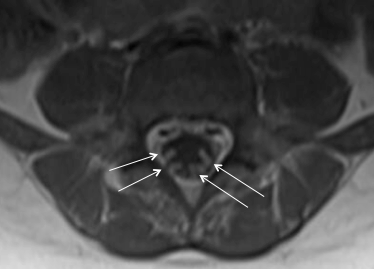

Discussion: Guillain-Barré syndrome is an acute polyradiculoneuropathy typically characterized by symmetric ascending paralysis. It is thought to be due to an inflammatory demyelination of neurons following infection or immunization, but may be idiopathic as well. While older children and adults classically present with ascending weakness, paresthesias, and flaccid paralysis, this is often not the case in younger patients, who are more likely to present with ataxia or abnormal gait. In our case, the initial symptoms were simply gait and balance disturbance and there was relatively little progression over two weeks after the onset of symptoms. This subtle and atypical presentation can make the diagnosis more challenging. GBS is a diagnosis based on clinical presentation, but is supported by other findings, including absent reflexes, albuminocytologic dissociation in the CSF and enhancement of spinal nerve roots with contrast-enhanced MRI (Figure 1). While GBS is less common in children than adults (0.34–1.34 per 100,000 per year in children compared to an estimated 1.1-1.8 in adults), the general pediatrician should consider this diagnosis in young children with gait disturbance and a negative musculoskeletal workup. Early treatment with IVIG or plasma exchange can shorten recovery time in these patients.